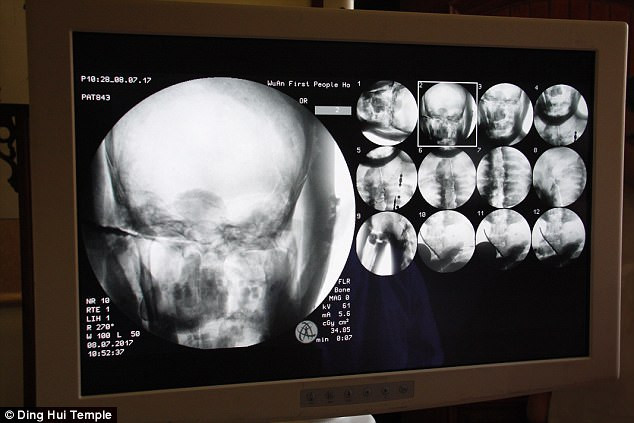

Các chuyên gia vô cùng bất ngờ khi tiến hành chụp cắt lớp vi tính xác ướp của vị đại sư Phật giáo sống cách đây 1.000 năm. Kết quả kiểm tra cho thấy mọi thứ còn nguyên vẹn một cách đáng kinh ngạc.

Các chuyên gia tiến hành chụp cắt lớp vi tính xác ướp đại sư Từ Hiền trước sự chứng kiến của các nhà sư, phật tử và phương tiện truyền thông.

Những người có mặt tại sự kiện trên đều vô cùng bất ngờ khi các chuyên gia thông báo thi hài đại sư Từ Hiền vẫn còn đầy đủ xương và sọ não hoàn chỉnh.

"Chúng ta có thể trông thấy xương cốt đại sư vẫn còn chắc khỏe như xương của người thường", bác sĩ Wu Yongqing chia sẻ.

Theo bác sĩ Wu Yongqing, xương hàm trên, hàm dưới, xương sườn, cột sống và tất cả khớp đều hoàn chỉnh. Điều này thật đáng kinh ngạc.